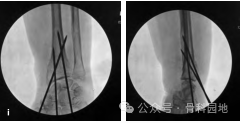

6、在干骺端长节段骨折中,可以使用大倾斜的克氏针固定。但克氏针可能会滑入髓腔很难固定(下图a-d)。